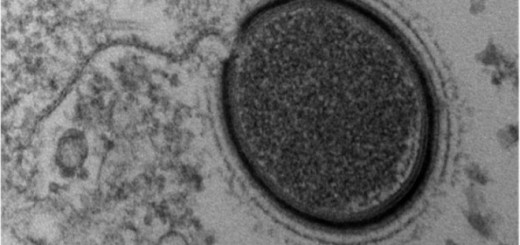

Οι ερευνητές, με επικεφαλής τον καθηγητή Ρέιμοντ Στίβενς του ερευνητικού Ινστιτούτου Scripps και τον Μπράιαν Κομπίλκα του πανεπιστημίου Στάνφορντ, που δημοσίευσαν τις δύο σχετικές μελέτες στο περιοδικό «Nature», δήλωσαν ότι η λεπτομερής χαρτογράφηση της δομής των υποδοχέων οπιοειδών, με τη βοήθεια της τεχνικής της κρυσταλλογραφίας ακτίνων-Χ, διευκολύνει πλέον την ανάπτυξη νέων φαρμάκων σε σημαντικό βαθμό.

Υπάρχουν διάφορα είδη υποδοχέων οπιοειδών και ο τρόπος που συνδυάζονται μεταξύ τους, δεν έχει ακόμα κατανοηθεί πλήρως από τους επιστήμονες. Για παράδειγμα, οι υποδοχείς «μ» ρυθμίζουν την ευχαρίστηση και την ανακούφιση από τον πόνο, ενώ αντίθετα οι υποδοχείς «κ» την κατάθλιψη και τη δημιουργία ψυχεδελικών εμπειριών.

Οι ερευνητές κατάφεραν να ανακαλύψουν τη δομή τόσο των υποδοχέων «μ» όσο και των «κ». Μάλιστα, στην περίπτωση των δεύτερων υποδοχέων οι ερευνητές ευελπιστούν ότι θα ρίξουν περισσότερο φως στον τρόπο που ο εγκέφαλος παράγει την αντίληψη και τη συνείδηση, καθώς και γενικότερα τον τρόπο που αντιλαμβάνεται την πραγματικότητα.